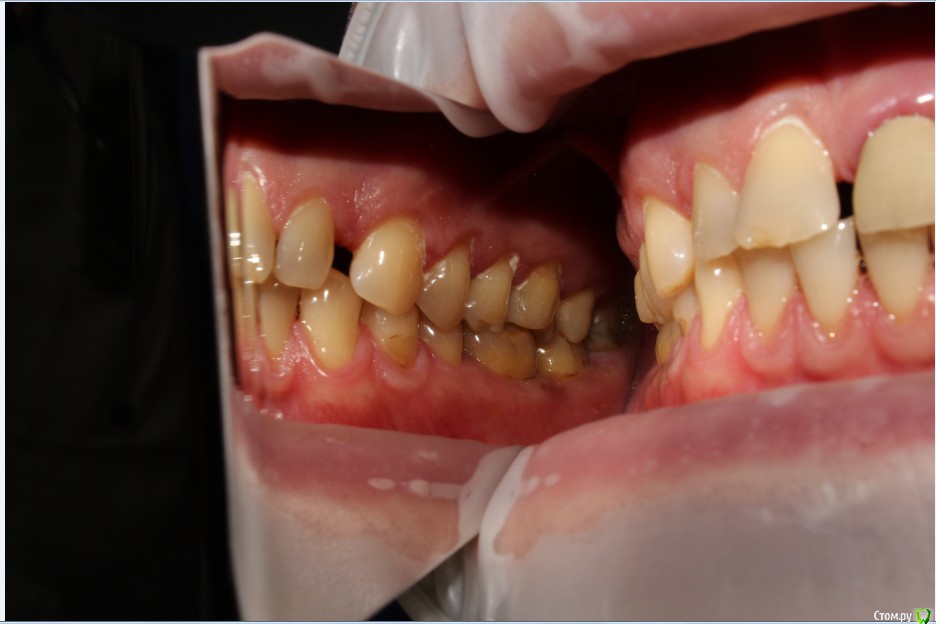

Рустам Опубликовано 20 июля, 2015 Поделиться Опубликовано 20 июля, 2015 Здравствуйте коллеги! Подскажите по клиническому случаю пожалуйста. Обратился пациент в клинику с подвижной коронкой на зубе 2.1, на рентгене диагностирован перелом корня, планируем удаление с одномоментной имплантацией и желательно с немедленной нагрузкой. Система имплантатов "Osstem", на этой системе я ранее не протезировал (работал с "Mis" и "Super Line") и вообще ранее немедленно не нагружал имплантаты. Хирург назначил удаление и иплантацию на 23.07, я смогу принять пациента только 24.07 утром, необходимо заказать временный абатмент, подскажите какой именно из каталога нужно заказать?Имплантолог заказал два имплантата Osstem TSIII SA диаметром 4,0 и 4,5.Я планирую делать временную прямым способом по ключу снятому со старой коронки во рту. Может лучше через оттиск заказать лабораторную временную?P.S. пациента эстетически все устраивало, ортодонтию не хочет. Ссылка на комментарий